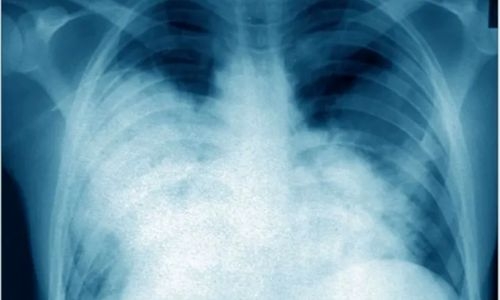

"The Legionella bacterium's genome was discovered," she informed reporters. "The most likely pathogen is Legionella pneumophila."However, she stated that the results are preliminary and that additional testing is being carried out. Legionnaires' disease is a severe form of pneumonia caused by inhaling Legionella bacteria in minute droplets of water or accidentally swallowing Legionella-contaminated water.

Although most people recover from Legionnaires' disease with antibiotics, certain patients, notably those who are immunocompromised or have chronic lung illnesses, can develop deadly consequences. According to the World Health Organization, the instances arose between August 18 and August 25, with patients complaining of fever, muscle aches, abdomen pain, and difficulty breathing, in addition to pneumonia symptoms. Eight of the 11 cases were clinic employees, while three involved patients. Three of the four deaths happened among health staff. According to the WHO, the median age of the cases is 45, with seven males. Ten persons, including the four fatalities, had underlying illnesses that put them at risk for serious disease.